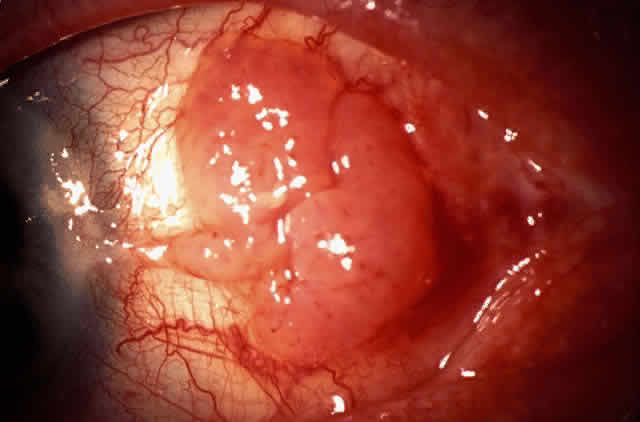

In the conjunctiva, HPV can induce papillomatous lesions (papillomas and inverted papillomas) and epithelial dysplastic lesions consisting of conjunctival intraepithelial neoplasia and squamous cell carcinoma. Conjunctival papillomas were traditionally divided into infectious, limbal, and inverted types; however, current data suggest that all types have a viral etiology. All sites of the conjunctiva can be affected, and involvement of the contiguous epithelium of the lacrimal canaliculus, lacrimal sac, and nasolacrimal duct has been noted to occur.38,61,62 Conjunctival papillomas can be pedunculated or sessile and are typically shiny, flesh-colored, and papillomatous (Fig. 1). Each papillary frond has a vascular core that is easily seen through the nonkeratinized epithelium. The papillomatosis is responsible for the typical appearance of evenly spaced vessels throughout the lesion. If keratinized, these lesions may appear whitish and dull. Papillomas can be either unilateral or bilateral, and they can be either solitary or multifocal (Fig. 2). Inverted papillomas are the least common type of papilloma in all sites, but they constitute a larger portion of lacrimal sac tumors than other periocular tumors.63,64

Fig. 2. Confluent conjunctival papillomata in patient with multiple recurrent lesions and chronic immunosuppression after multiple renal transplants.